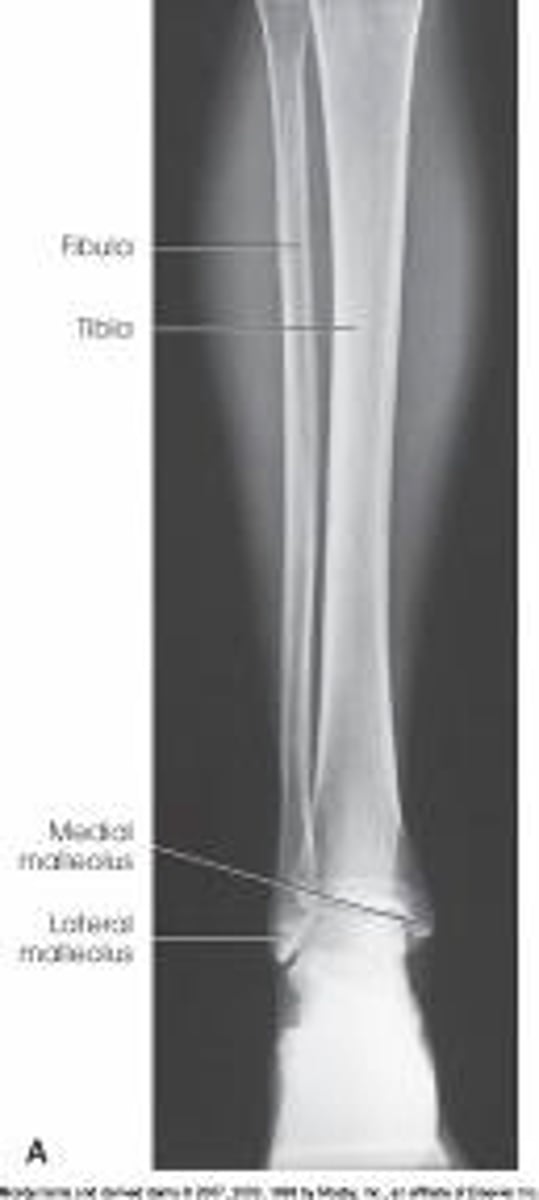

An AP of the knee and proximal leg

What is needed to complete the projection of the lower leg in the image below?

Nothing. This is a complete projection.

An AP of the ankle and distal leg

A lateral projection of the knee